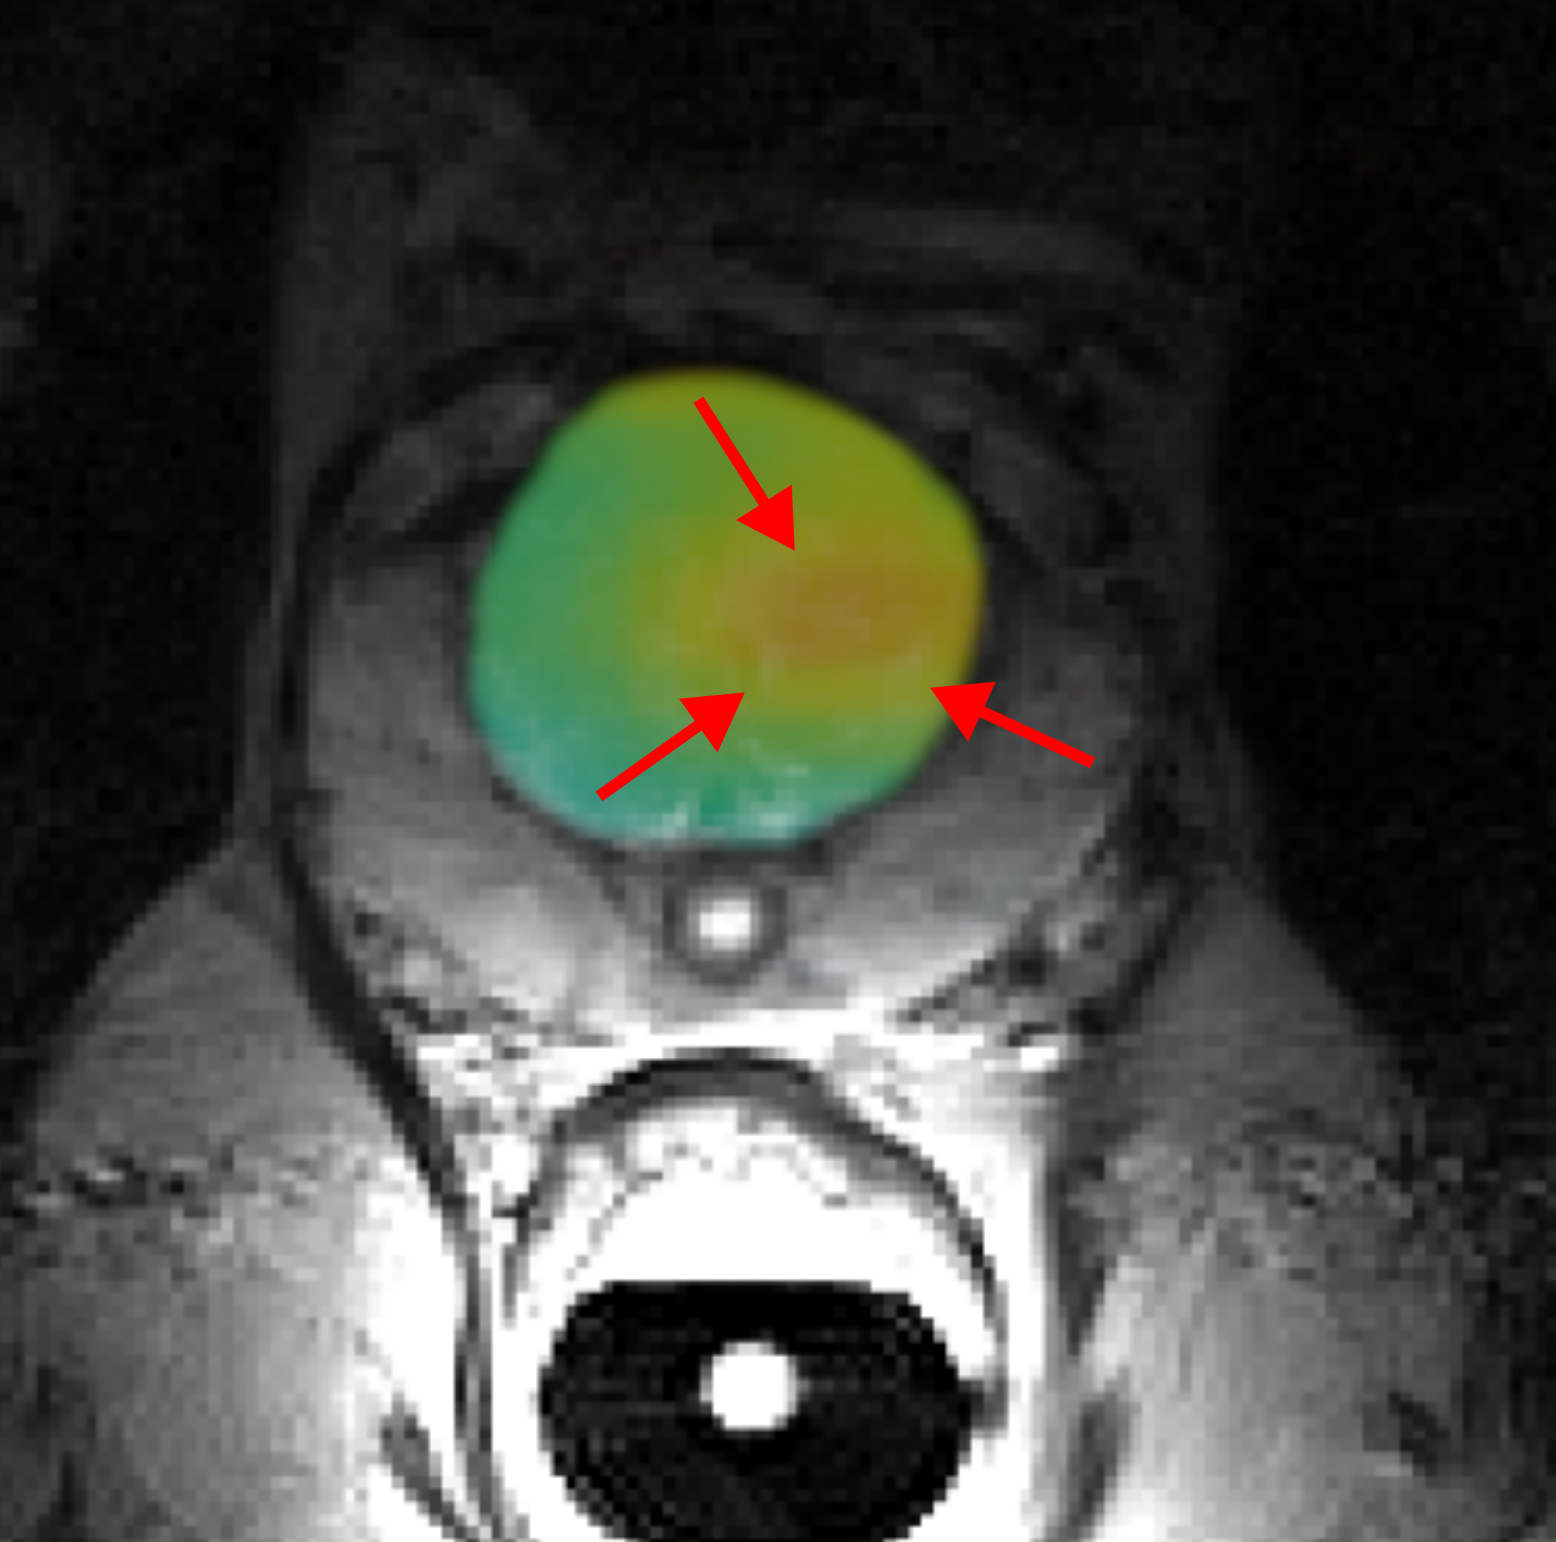

Mit Hilfe von speziellen MRT-Verfahren beispielsweise auf der Basis der körpereigenen Substanz Pyruvat kann der Tumorstoffwechsel untersucht und sogar quantifiziert werden. Dazu muss die Substanz so aufbereitet werden, dass ihr schwaches MRT-Signal um den Faktor 10.0000 und mehr verstärkt wird. Bisher dauerte diese sogenannte Hyperpolarisation einige Stunden und war technisch sehr aufwändig, so dass ein klinischer Einsatz nur in wenigen Studien untersucht werden konnte – diese Studien zeigten jedoch bereits das große Potenzial für die Onkologie.

Um die neue Technologie für den Einsatz in der klinischen Routine zu optimieren und anschließend am Patienten zu testen, fokussiert sich jeder Klinikstandort auf unterschiedliche Tumorarten. Das Universitätsklinikum Freiburg konzentriert sich in seiner Teilstudie auf das Prostatakarzinom. „Der veränderte Stoffwechsel ist ein wichtiger Indikator, mit dem aggressive Prostatakarzinome von weniger aggressiven unterschieden werden können“ sagt Prof. Dr. Christian Gratzke, Ärztlicher Direktor der Klinik für Urologie des Universitätsklinikums Freiburg. Schon jetzt hat die MRT einen wesentlichen Anteil an der Diagnostik von Patienten mit einem Prostatakarzinom. „Mit hyperpolarisierten Kontrastmitteln könnten wir das Diagnostik-Spektrum deutlich erweitern und so die Krebstherapie künftig noch individueller anpassen“, sagt Prof. Dr. Fabian Bamberg, Ärztlicher Direktor der Klinik für Interventionelle und Diagnostische Radiologie am Universitätsklinikum Freiburg.